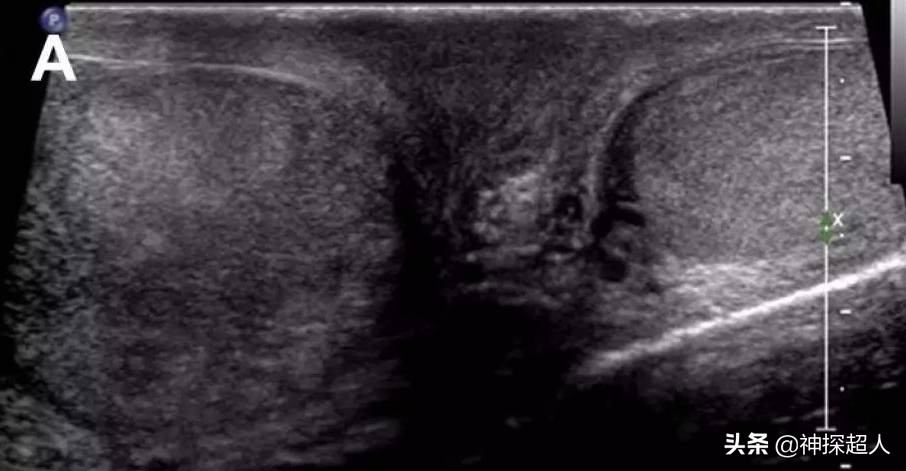

右侧*丸睾**扭转声像图

彩色多普勒超声: 为诊断*丸睾**扭转的首选检查方法,准确率接近90%。超声检查可显示*丸睾**血流信号减弱或消失,还可以帮助区分扭转与附睾炎。*丸睾**扭转者在早期,超声下可见*丸睾**回声轻度肿大,彩色血流信号减少。扭转继续或加重,则*丸睾**明显增大,彩色血流信号明显减少或消失,*丸睾**周围出现少量液性回声,阴囊壁软组织增厚。晚期病例,*丸睾**坏死内部回声不均匀,周围液性回声增多,彩色血流信号消失。

超声检查提示:*丸睾**肿胀近似球形,回声减低,CDFI于*丸睾**内未探及血流信号。